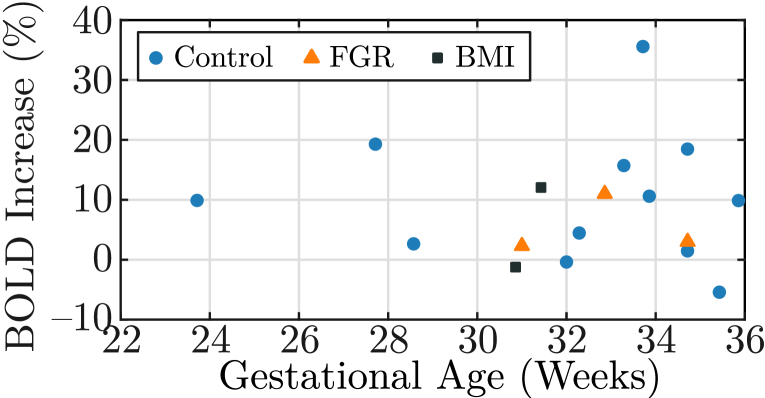

Fig. 5 shows a scatter plot of the hyperoxia response for all subjects in the test set and two examples of the BOLD signal time course in the produced placenta segmentation label maps. In the control subjects (N=), we observe an increase of . The observed increase for the healthy controls is consistent with previous studies that demonstrated an increase of (N=) [15] and from to throughout gestation (N=) [14].

Segmenting each volume in the BOLD MRI time series can be advantageous for clinical research assessing whole-organ changes as it eliminates the need for registration. Registration algorithms are affected by fetal motion and may require discarding a significant number of volumes [2, 25], potentially losing important signal information. We illustrate one possible study in assessing placental response during hyperoxia, observing an increase in signal intensity consistent with prior work. However, our cohort is limited, and several factors, including maternal position, gestational age, and contractions are covariates not considered.